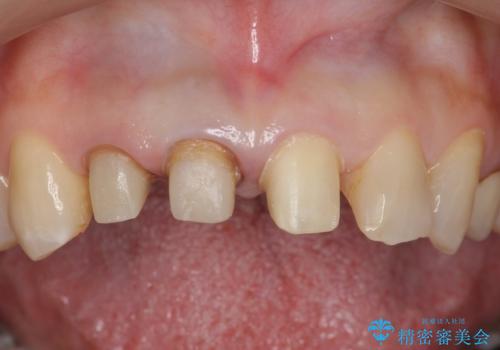

右上の前歯のみの被せなおしですと、右上の前歯が反対側に比べて極端に大きくなってしまうことを説明し、左上の前歯も併せてセラミックにすることにしました。

右上の前歯二本、左上の前歯1本をセラミックにし、正中の前歯を2本連結しました。

連結のデメリットはフロスができなくなってしまうことになるため、歯間ブラシを使用していただいてメンテナンスしていただくことになります。7

また、見た目の歯と歯の分離感も、連結しない方が表現することが可能です。